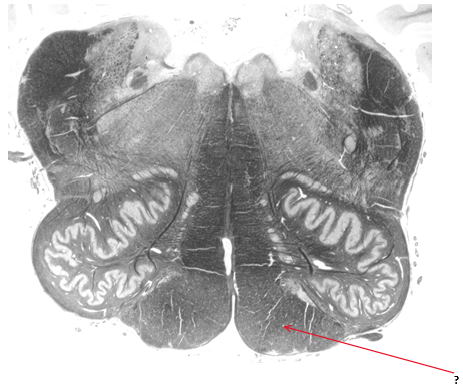

Name this and state its function within its 2 parts.

Olive.

Inferior: integrates motor and sensory function

Superior: sound localisation.